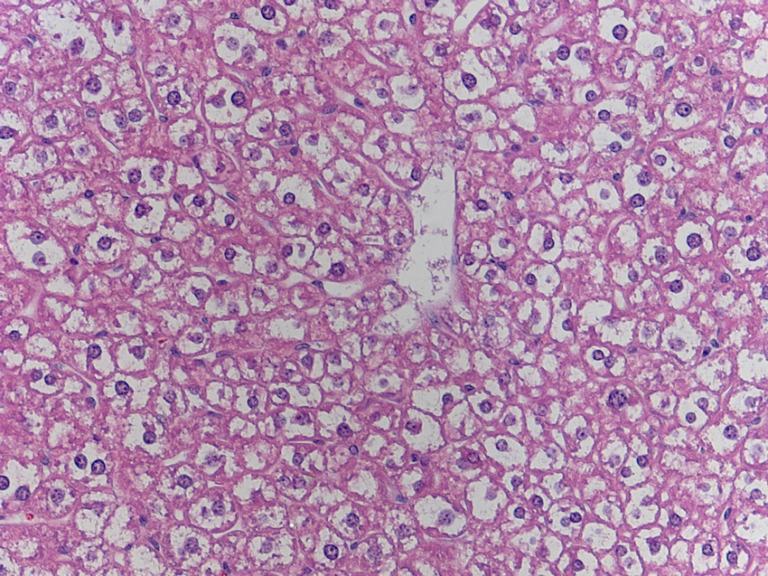

KIDNEY TISSUE:

Kidney tissue examples:

The Glomerulus, plural Glumeri, is a group of capillaries (tiny blood vessels) where waste is filtered from the blood.

kidney cells found in my slides: